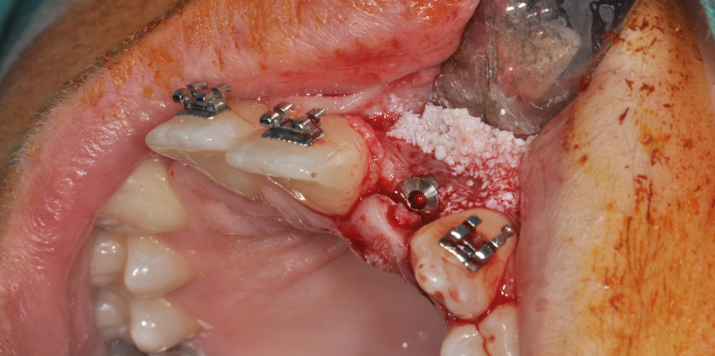

→ Pose du ou des implants

Durant cette étape, le praticien pose les implants dentaires pour remplacer les racines manquantes. À l’issue de cette intervention, vous sentirez des implants couverts par la gencive, et qu’ils sont mis en “nourrice” : cela permet à l’os de cicatriser autour des implants.

L’implant dentaire est placé dans la mâchoire sous anesthésie locale dans la majorité des cas, parfois sous anesthésie générale.

- La chirurgie implantaire guidée

La chirurgie implantaire

Vidéo de la chirurgie implantaire